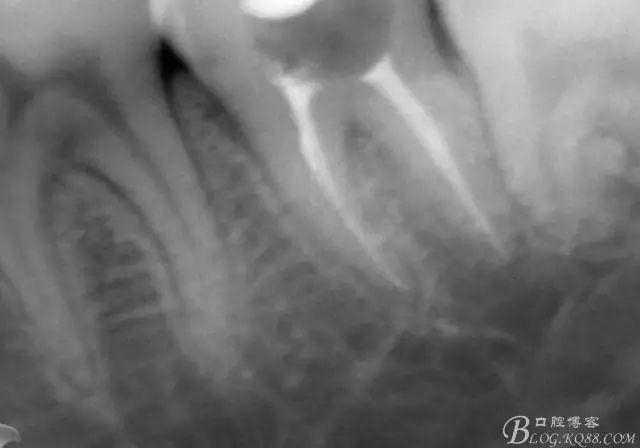

第四次復(fù)診,37叩(—)。此次行冠部修復(fù),因涉及38的拔除,患者不愿拔除,與患者介紹修復(fù)材料與方法,擬37E.max嵌體修復(fù),術(shù)前常規(guī)簽修復(fù)知情同意書。

一周后復(fù)診,37臨時(shí)充填物完好。去除臨時(shí)充填物,清潔基牙,試戴嵌體,就位良好,邊緣密合。取下嵌體,常規(guī)處理,9.5%HF處理20S,沖洗一分鐘,95%酒精蕩洗5分鐘?;劳磕?7%的磷酸凝膠,釉質(zhì)區(qū)域酸蝕30S,本質(zhì)區(qū)域15S。粘固用的是3M第八代粘接劑套裝,照說明書逐步操作。最終固化時(shí)涂滿阻氧劑,每個(gè)牙面最少光照30S,光固化燈用漸強(qiáng)模式。常規(guī)調(diào)合,配合硅膠尖套裝拋光。術(shù)后常規(guī)醫(yī)囑,不適隨診。